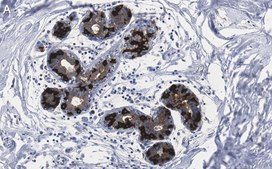

Immunohistochemistry (Paraffin) Analysis: A 1:100 dilution from a representative lot detected FASN in human breast tissue sections.